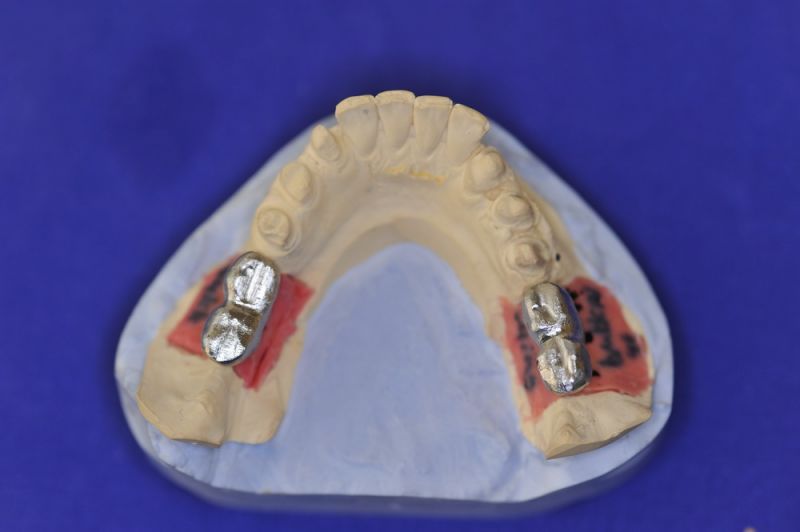

Es wurden sechs Implantate inseriert und diese wuchsen, trotz vielerlei Bedenken knöchern ein.

Nun stellte sich heraus, dass der Abstand zwischen den Implantaten sehr gering war, weil die Einschubrichtungen der Aufbauten sich zum Teil gegenseitig im Wege standen. Konfektionierte Teile mussten individuell umgeschliffen werden, dabei das Ziel, den Biss korrekt einzustellen nicht aus dem Auge zu verlieren.

Heute war nun Gerüsteinprobe, mit all den Problemen der Umsetzung zwischen Laborsituation und Mundsituation. Siehe Stichpunkt "Schnittstellenproblematik"! was bei Zähnen, auf Grund deren Eigenbeweglichkeit im Kieferkochen kein Problem wäre, ist bei drei unbeweglichen Implantaten ein Riesenproblem. Darüber spricht nur in aller Regel Niemand! Es musste viel fein nachgearbeitet werden.

Eine Arbeit, bei der der Einsatz an Arbeitszeit überproportional hoch ist, aber mit weniger das gewünschte Ergebnis nicht zu erreichen sein wird. Letzte umfangreiche Besprechungen mit der Zahntechnikermeisterin, bevor es jetzt an die endgültige Herstellung der beiden Rekonstruktionsblöcke geht.